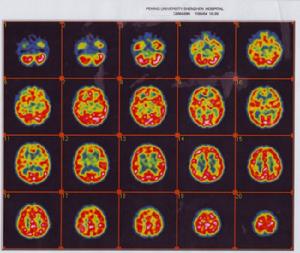

3.影像學研究結構性腦影像技術(CT和MRI)發現孤獨症患兒大腦總體積和左右側腦室體積均顯著大於對照組而腦幹及右側前扣帶回的體積明顯減少。功能性腦影像技術(SPECT和PET)發現患者的大腦皮質代謝呈瀰漫性減弱及局部腦血流灌注降低但樣本例數不多尚不能確切解說孤獨症的認知異常。

童年孤獨症有些研究發現孤獨症與腦器質性損害有關如果這些損害發生於產前或圍生期則本症症狀出生後即出現;如果發生於幼兒期,則出生後可有一段正常發育期。約有2%~5%患兒伴有脆性X染色體綜合徵有15%~50%患兒伴有癲癇發作EEG誘發電位、CT均可發現非特異性異常(不足以作為診斷依據)MRI也有非特異性異常,有人在MRI中發現患者有小腦蚓部小葉發育不良,認為可能有特異性但未得到別人證實。PET發現許多腦區有葡萄糖代謝增加,但亦非特異性。